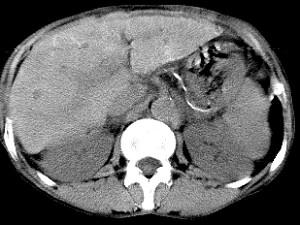

问题 男,40岁有血吸虫感染史,腹胀不适,食欲减退,CT扫描所见如图,最可能的诊断是 ( )

选项 A.肝炎后肝硬化 B.血吸虫后肝硬化 C.酒精性肝硬化 D.胆汁性肝硬化 E.脂肪肝

答案 B